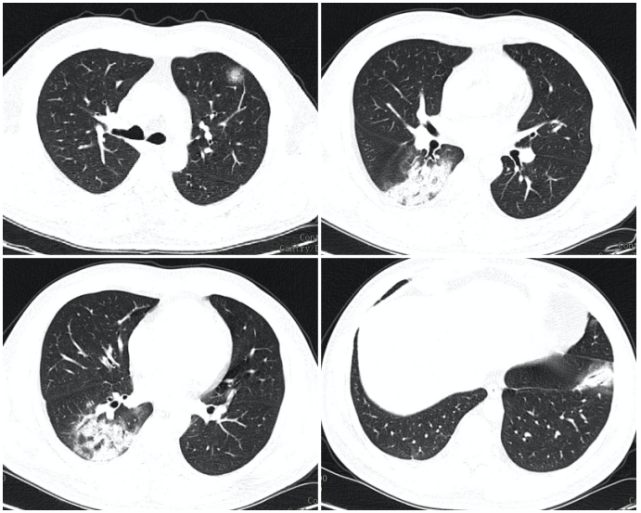

而新冠肺炎早期呈现多发小斑片影及间质改变,以肺外带明显,进而进展为双肺多发 GGO、浸润影,严重者可出现肺实变,胸腔积液少见。

实际情况是各种病原体 CAP 的影像学表现有重叠,有很多不确定因素,大部分情况下只能缩小鉴别诊断范围,很难明确病原体(图 1、2)。

图 2 男性 37 岁,2020 年 1 月初武汉旅行归来,发热咳嗽 5 天,确诊为新冠肺炎